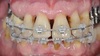

Deux attelles métalliques sont posées en haut et en bas pour conserver les résultats du traitement orthodontique. Le métal derrière les dents génère un ombrage disgracieux et l’esthétique du sourire est décevante.

Une nouvelle attelle en résine renforcée par de la fibre de verre, confectionnée et posée au maxillaire par le cabinet ZEN de PARIS, améliore beaucoup l’esthétique du sourire.

L’attelle en métal s’est décollée après 13 ans derrière les incisives du bas qui ne présentent plus de mobilités. L’occlusion, la santé parodontale et l’esthétique ont été obtenus dans ce traitement. Seuls les patients motivés et disciplinés peuvent suivre un tel traitement.